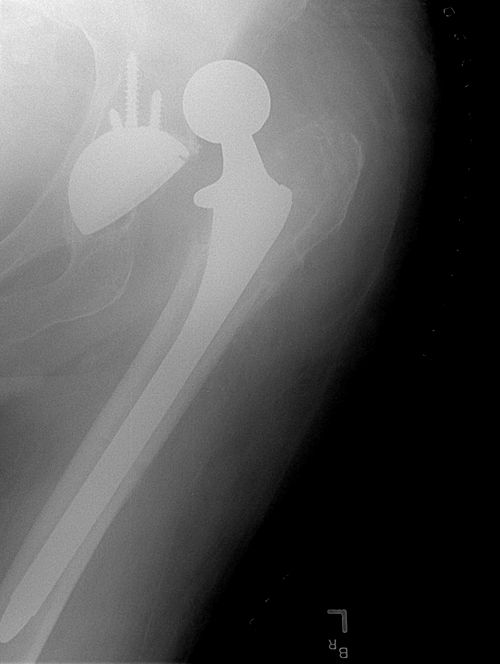

Luksasjon etter total hofteprotese (THP) er en alvorlig, men relativt sjelden komplikasjon som typisk oppstår som følge av feilbevegelser, traumer eller utilstrekkelig etterlevelse av post-operative forholdsregler. Etter en proteseoperasjon endres den naturlige anatomien og stabiliteten i hofteleddet, noe som gjør leddet mer sårbart for dislokasjon. Belastning på kapselen som ble incisert under kirurgien, kombinert med utilstrekkelig muskulær og ligamentær støtte, øker risikoen betydelig¹,².

Diagnosen stilles som regel ved hjelp av konvensjonell røntgen av bekken og hofteledd. Dersom implantatets posisjon må vurderes nærmere, kan det være aktuelt å supplere med CT for å identifisere malposisjonering eller impingement-problematikk².